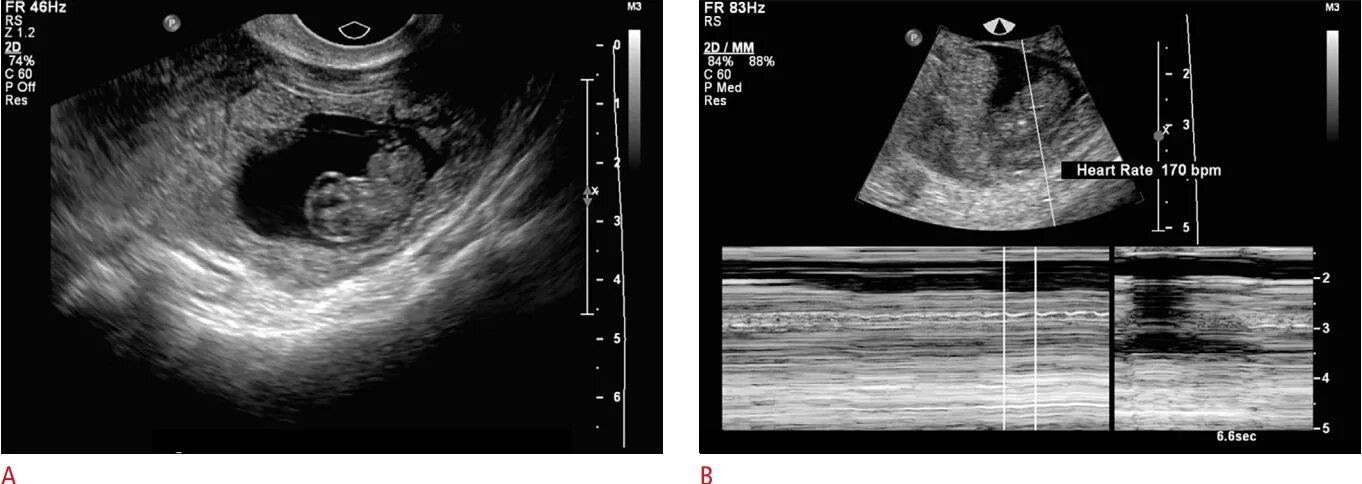

Можно ли на узи увидеть внематочную беременность